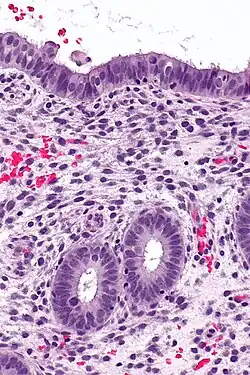

Endometrium | Micrograph showing proliferative phase of endometrium. | Category: Histology of endometrium | endometrium |

![]() |